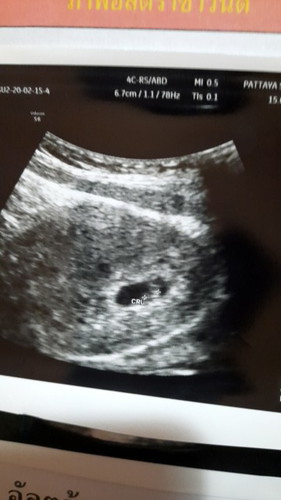

บ้านนี้7w6dคะเจอตัวน้องแล้วแต่ยังไม่ได้ฟังเสียงหัวใจน้องเลยคะ

บ้านนี้ 6 w คลอด 26 ตุลาค่า ได้ฟังเสียงหัวใจแล้ว แต่ตัวจิ๋วมากเลยค่า 🥰

บ้านนี้คุณหมอกำหนด 1 ตุลาคมค่ะ